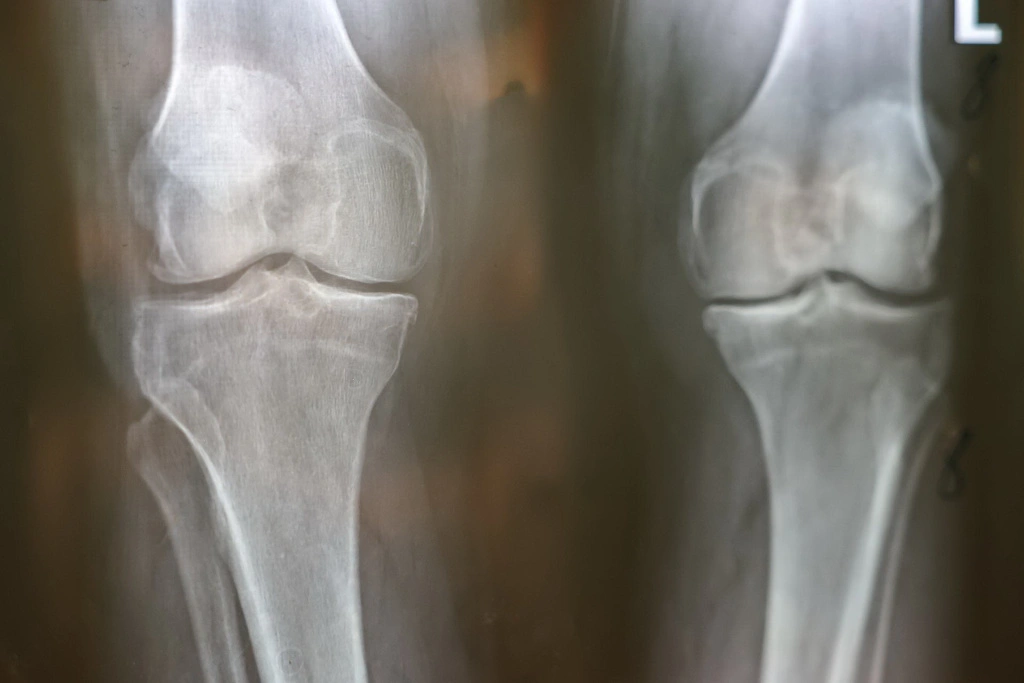

На снимках: операции по эндопротезированию

в Белгородской областной больнице святителя Иоасафа